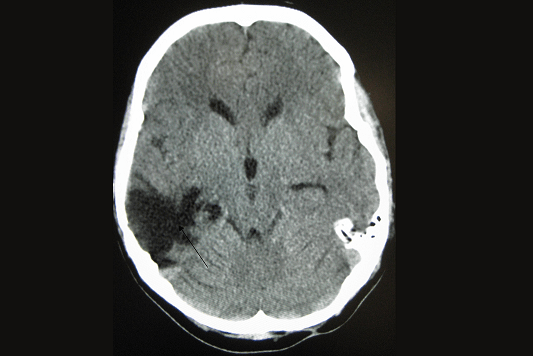

HEMORRAGIAS CEREBRALES

Las hemorragias cerebrales son una emergencia médica que ocurre cuando se produce un sangrado dentro del cerebro o en sus alrededores. Este tipo de hemorragia puede causar daños graves y permanentes, por lo que es crucial un diagnóstico y tratamiento rápidos.